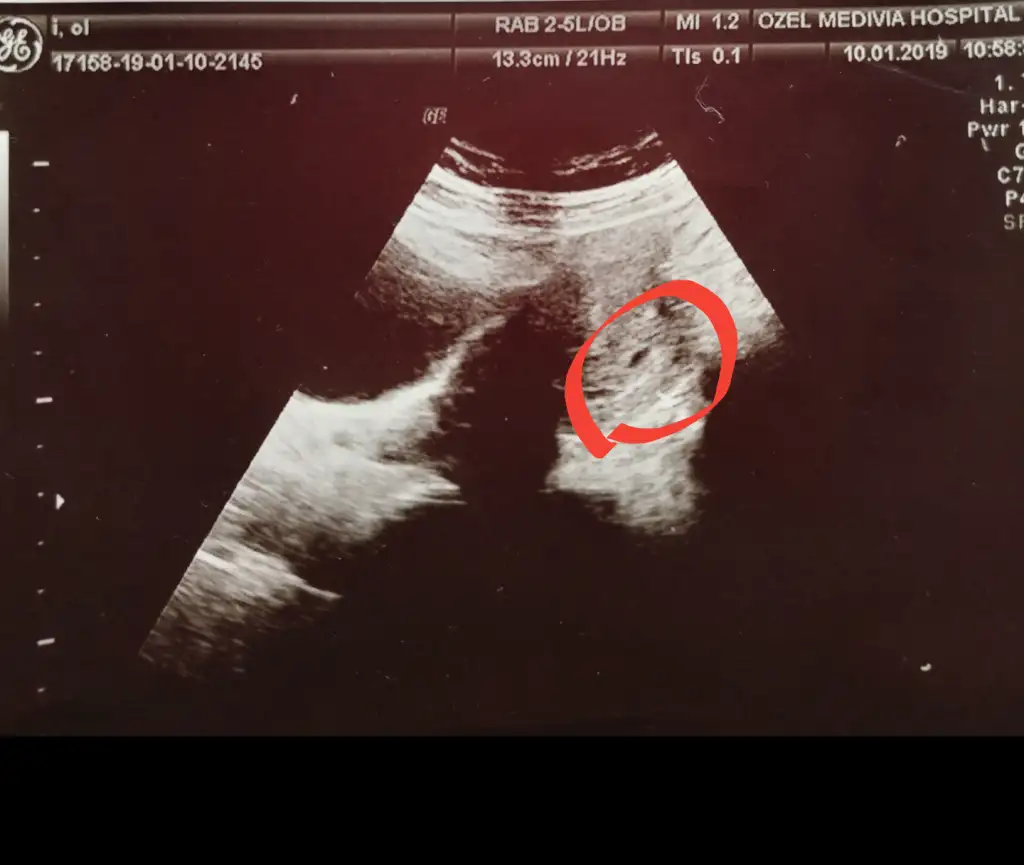

Bana da hafta içi tekrar gel demişti ama ben haftaya çarşambaya randevu alabildim o zaman kalp atışı falan da duyabilirm inşAllah siz bu cuma mı gidiceksinizSeninle aynı zamanda hamile kalmışız :) Doğum tarihimiz de 1 gün arayla. Ben de 4+7 iken gittim yani 5.haftamı doldurmuştum geçen cuma. Zar zor buldu karından ultrasonla. Bu cuma bir daha çağırdı inşAllah bebeği de görürüz kesede. Ultrason fotoğrafım aşağıdaki gibi küçücük kese.

Canım ben de 4+7 iken gittim geçen hafta. Yani 5 haftamı doldurmuştum. Sanırım senle aynıyız. Karından gözüktü ama zar zor. Aşağıdaki foto gibi. Çok küçük kese. Bu cuma yine gelmemi söyledi.Eki Görüntüle 2545477